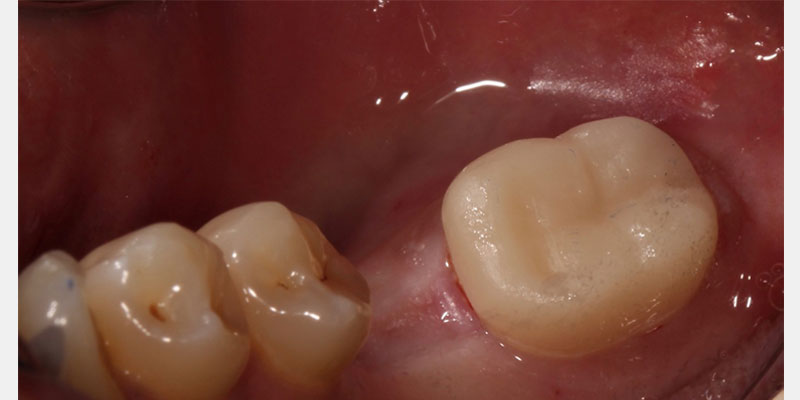

Endocrown restorations can be designed and fabricated using CAD/CAM technology and delivered in a single-visit appointment. Fabricating a provisional can be challenging due to the lack of traditional retentive features in an endocrown preparation. Studies performed that have involved fabricating a provisional for an endocrown preparation have utilized various materials, including Cavit-1 and acrylic-based provisional materials.6

Early results have shown that the endocrown has a high success rate, especially in molar teeth. A seven-year study comparing traditional crowns on endodontically treated teeth with endocrown restorations found success rates of 99.78% for traditional crown restorations and 98.66% for endocrown restorations.7 Also, a retrospective study looking at severely broken-down teeth with endocrowns found a survival rate of 99.0% and a success rate of 89.9%.8

Endocrown is a unique type of restoration that is predictable in restoring complex endodontically treated teeth. It is another option to consider when developing a treatment plan to restore endodontically treated teeth.